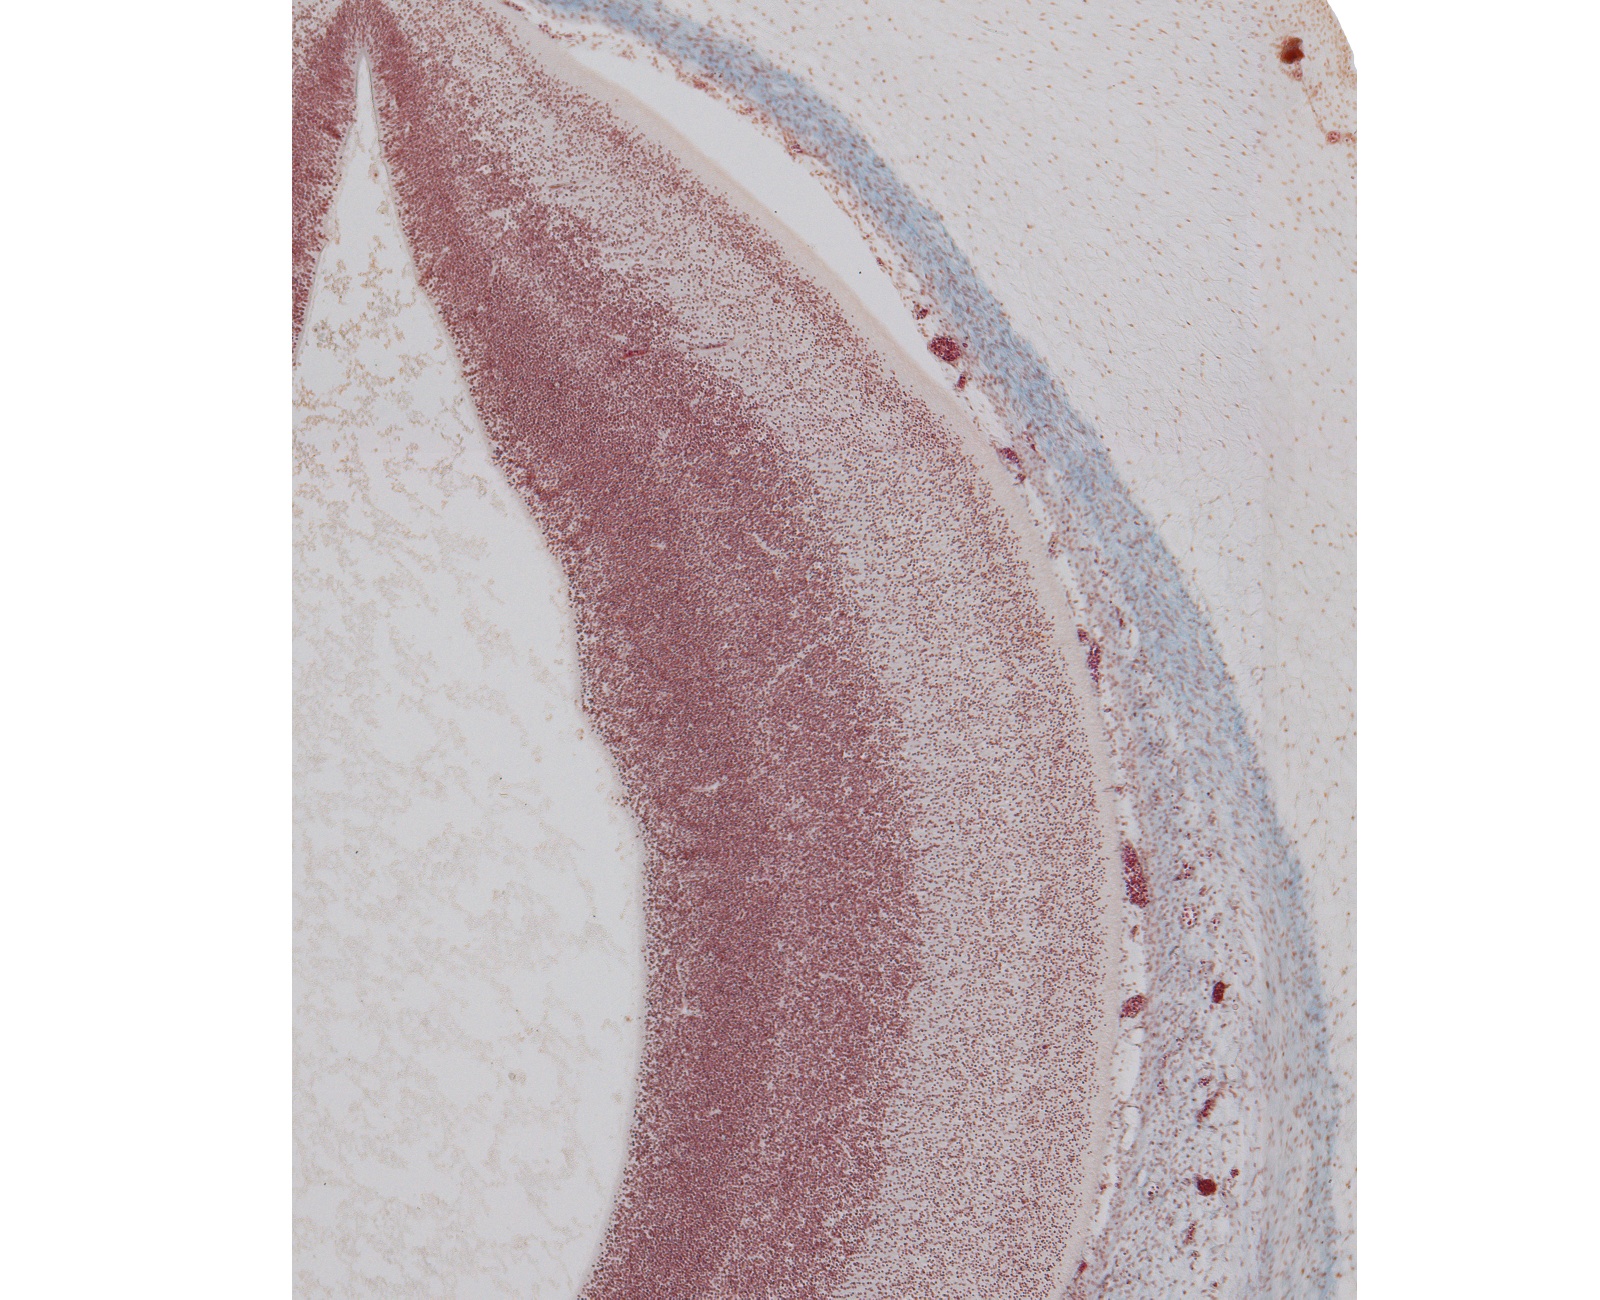

Tissue

–

Tectum of Mesencephalon

Carnegie Embryo #9226

Location:

7-01-01